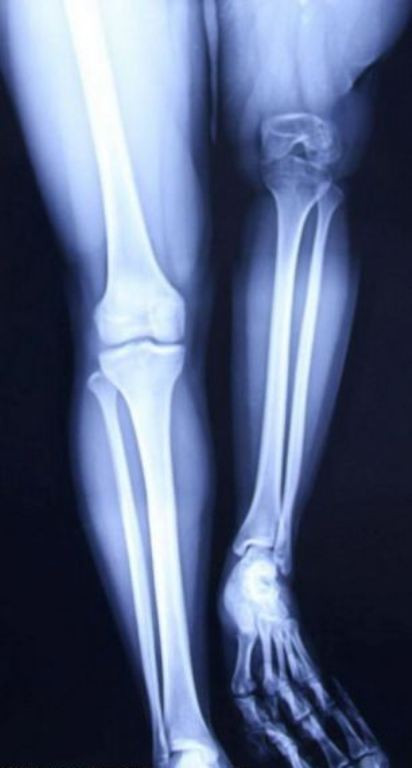

Hình ảnh Xu với đôi chân ngắn dài không bằng nhau trước khi phẫu thuật kéo dài chân.